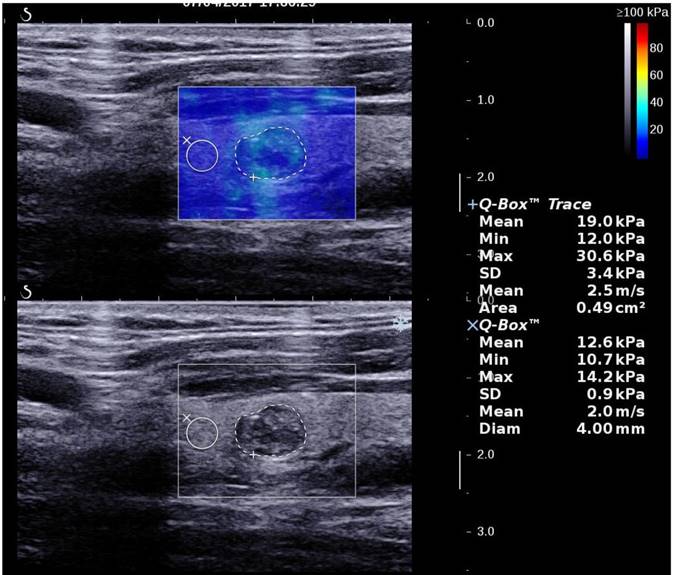

2D SWE examinations were performed by using the same probe of the AixPlorer US system in B-mode ultrasound examinations. This probe was applied in completely contact with the cervical skin with very light pressure to show the longest diameter of the thyroid nodule in sagittal section and kept more than 3 seconds. The region of interest (ROI) box of SWE color map was adjusted to include the nodule and the surrounding tissue (Fig. 1). The shear wave propagation velocity (SWV) of tissue in ROI can be measured, and turned to Young's modulus which is proportional to the tissue elasticity [23]. Results were expressed in kPa. The stiffer the tissue the higher Young's modulus was. A color map of tissue elasticity representing Young's modulus was obtained in ROI box ranging from 0 (dark blue, soft) to 100 kPa (red, hard). Quantitative elasticity values were measured using circular quantification ROIs (Q-box). One was adjusted to include all the portion of the thyroid nodule, the other was placed on the surrounding normal thyroid tissue. Three parameters were recorded for each nodule in sagittal: mean elasticity value of nodule (s-Emean), max elasticity value of nodule (s-Emax), ratio of mean elasticity value of nodule and surrounding normal thyroid tissue (s-Eratio). Then the relevant elasticity values were obtained in transverse section (t-Emax, t-Emean, t-Eratio).

Figure 1

A thyroid papillary carcinoma in sagittal section by 2D SWE with Young's modulus measured in the lesion and ratio with the surrounding tissue